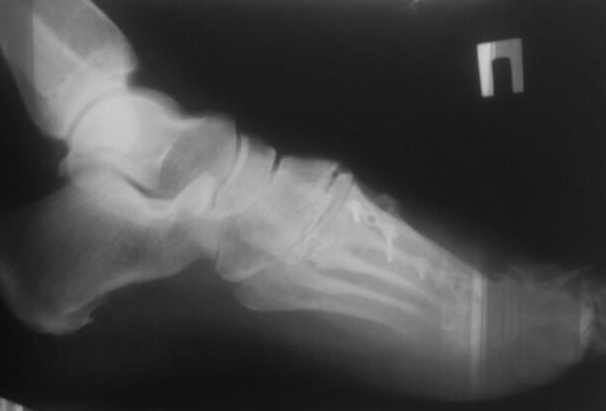

женщина средних лет, оперирована около года назад

Неутолимое желание поставить больше железок. 6 или 7 винтов и 2 пластины на одну плюсневую. Первичных снимков нет, но можно предположить, что 2 остеотомии привели к значительному укорочению М1. В результате - переходная метатарзалгия. Была или нет до операции деформация центральных пальцев тоже не знаем. Сейчас видны молоткообразная деформация второго пальца с преобладанием его длины над первым, перекрест второго и третьего пальцев. Если выпрямить второй - станет еще длиннее. А выпрямить может помешать отклоненный кнутри третий палец - второму некуда улечься. Поэтому нужно думать об остеотомии 2-4 плюсневых для устранения метатарзалгии (фиксированный или нефиксированный Вейль, DMMO - чем владеете), коррекции молоткообразной деформации второго (с его укорочением) и варусной деформации третьего пальца (возможно и четвертого, если будет мешать выпрямить третий). На болезнь Фрайберга не очень похоже. Скорее это подвывих пальца на некачественных снимках имитирует. В любом случае - моделирующая резекция - калечащая сустав операция. Декомпрессии за счет укорочения будет достаточно. Если есть возможность оперировать чрескожно - самый простой и беспроигрышный вариант.

Подвывих по 2-му лучу - большой. Может дополнительно подумать об удлинении разгибателей.